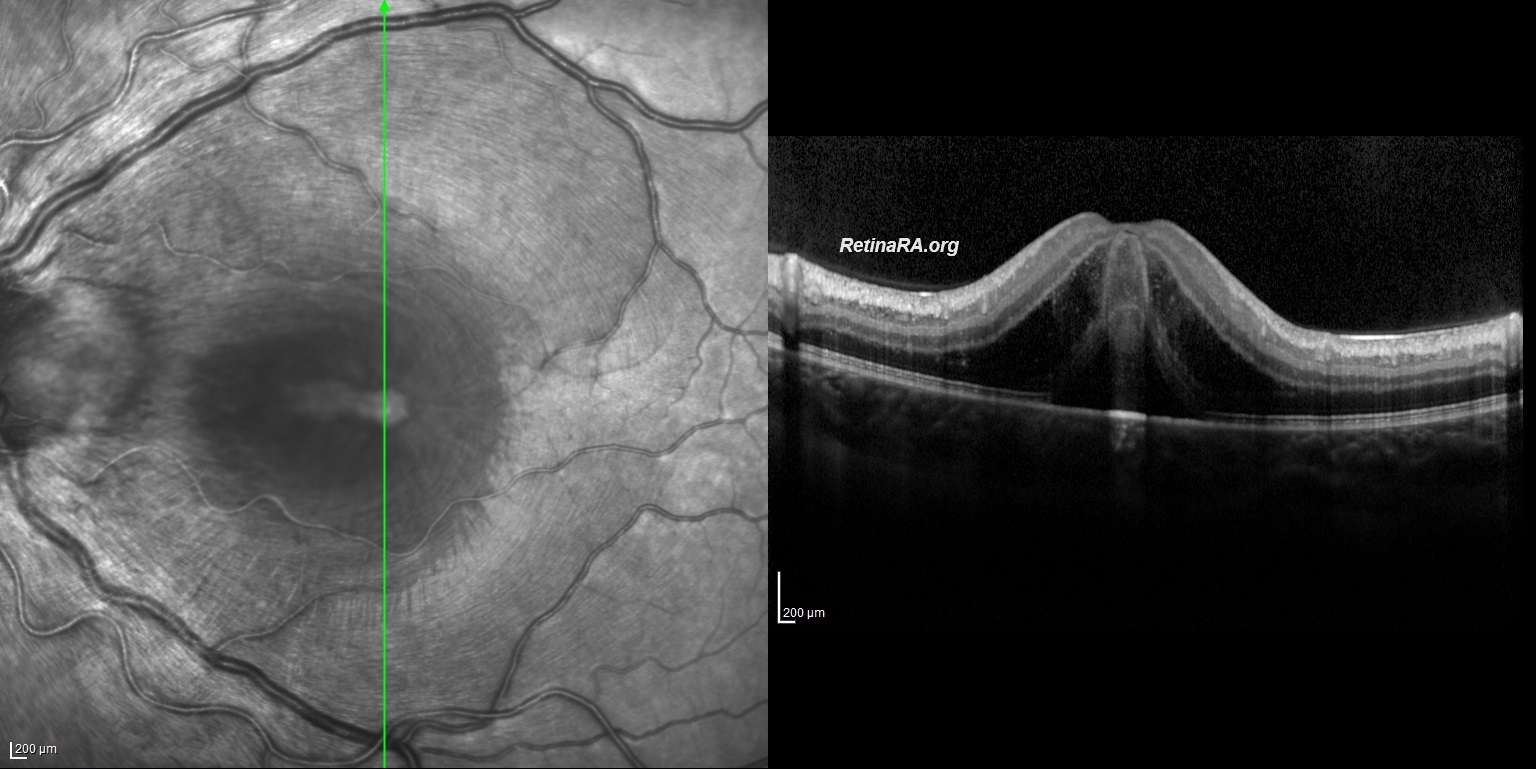

Macular edema was also present. The radial stretching lines seen in multicolor imaging and infrared reflectance imaging indicate fluid accumulation in Henle’s fiber layer. Vertical and horizontal OCT B-scans depict Macular edema with subretinal and intraretinal fluid. *Note that intraretinal fluid and exudate particularly accumulated in the Henle’s Fiber Layer. Neuroretinitis is characterized by an inflammation of the optic disc vasculature with exudation of fluid into the peripapillary retina. The lipid-rich component of the exudate is further able to penetrate into the Henle Fiber layer, creating what is clinically seen as a macular star pattern. Only the aqueous phase can pass through the external limiting membrane to accumulate beneath the neurosensory retina.

Bartonella Hanselea neuroretinitis was considered a preliminary diagnosis due to the history of being scratched by a cat 3 weeks ago. Empiric doxycycline and rifampicin were started. After the improvement seen on the 3rd day of antibiotic treatment and the negative results of Syphilis, toxocariasis and tuberculosis tests, 1 mg/kg methylprednisolone treatment was added to the patient. On the 9th day, Visual acuity improved to 20/30, healing continued and macular star appearance appeared. It is important to know that the macular star appearance in neuroretinitis occurs between the 7th and 10th days. The lipid-rich component of the exudate accumulated in the Henle fiber layer causes the appearance of the macular star. Some exudates settling on the outer retina, and ellipsoid zone alterations may also contribute to the macular star appearance.